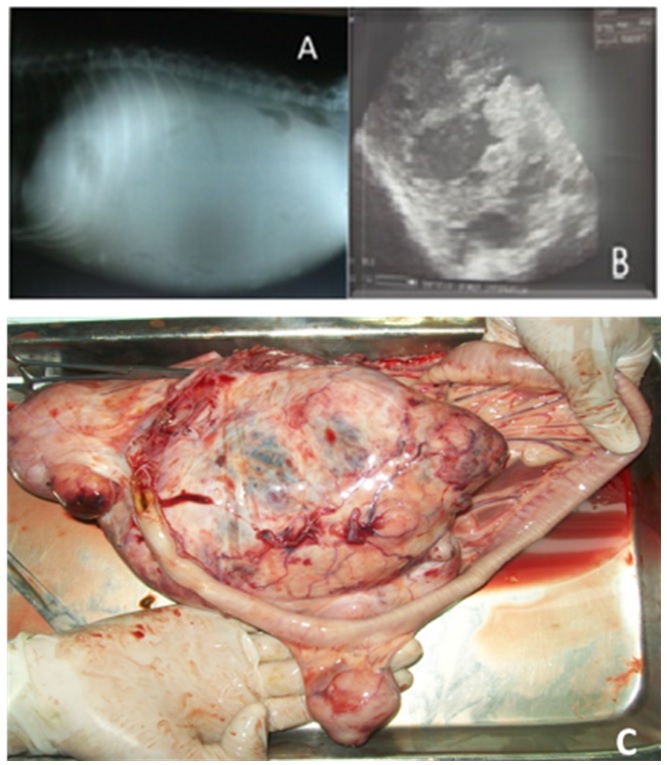

A side to side abdominal radiography was performed, showing widespread radiopacity and evidencing the presence of fluid in the abdomen (Figure 1A). By means of abdominal ultrasonography anechoic areas were observed in the abdominal mass (Figure 1B), suggestive of fluid content within the tumor, but the exam could not determine in which structure the mass was located. This way, an exploratory laparotomy was held, which revealed the mass location, attached to the small intestine mesentery. The patient died during the attempt to remove the mass owing to severe hemorrhage.

Pathological findings. The canine was taken for necropsy. A tumor mass was removed and was firm with irregular surface. It measured about 18 cm long by 13 cm wide (Figure 1C). Lymph nodes were edematous. It was noticed great tumor vascularization, which had a bloody uncoagulated content. When cut the mass appeared to have irregular consistency.